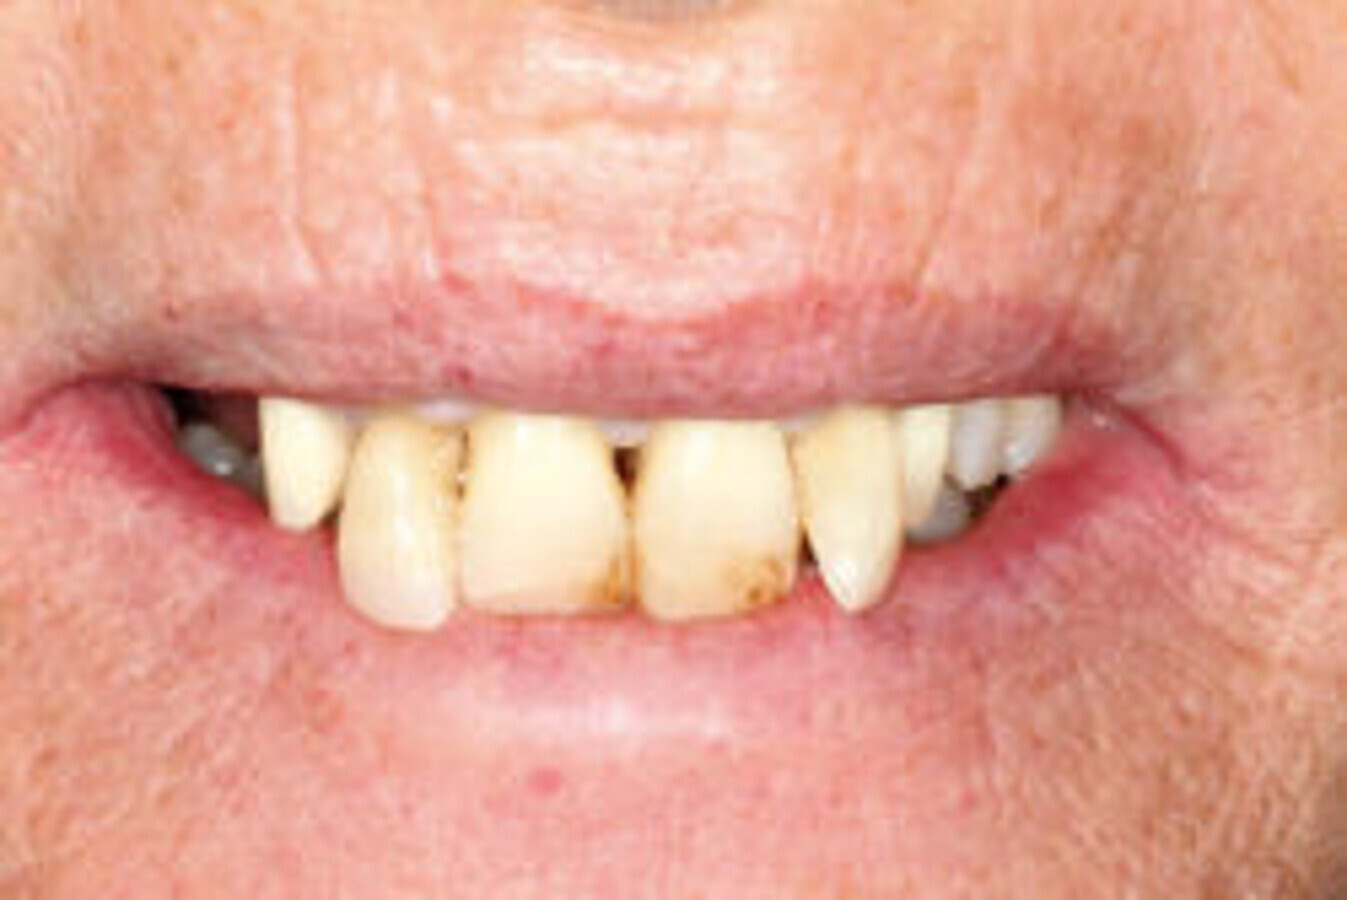

Slika 1: Početna situacija kod pacijenta – ekstraoralno.

58-godišnjakinja, nepušačica i sistemski zdrav pacijent kojeg je njen doktor dentalne medicine uputio u naš centar radi implanto-protetske terapije. Pacijenticu je uglavnom smetala loša estetika u gornjem frontalnom području, koje je karakterizirala visoka linija osmijeha i izražene anomalije položaja zuba (Slike 1. i 2.), kao i funkcionalna ograničenja kao posljedica neugode prilikom žvakanja. Tri zuba su nedostajala u gornjoj distalnoj regiji i to zubi 17, 15 i 27 koji nisu bili protetski opskrbljeni, dok je u donjoj čeljusti u distalnoj regiji nedostajalo pet zuba s obje strane u području premolara te su oni zamijenjeni djelomičnom mobilnom protezom. Svi preostali zubi u gornjoj i donjoj čeljusti bili su prema klasifikaciji „Proceedings of the World Workshop on the Classification of Periodontal and Peri-implant Diseases and Conditions 2017“ imali parodontitis stadija IV, a prosječna dubina sondiranja parodonta je bila 5,6 mm. 7 Prosječni indeks krvarenja (BOP) i srednji indeks plaka (PI) bili su 70 odnosno 80 posto. S obzirom na paradontološke parametre i mjere oralne higijene (vidljivi kamenac i naslage), oralna higijena pacijentice klasificirana je kao loša. Pacijentica je u drugoj ordinaciji liječena s dva implantata u desnoj maksilarnoj stražnjoj regiji kako bi se zamijenili prvi pretkutnjak i prvi kutnjak (Slika 3). Prema definiciji koju je Weißgold uveo 1977. godine, pacijent ima debeli biotip. 26